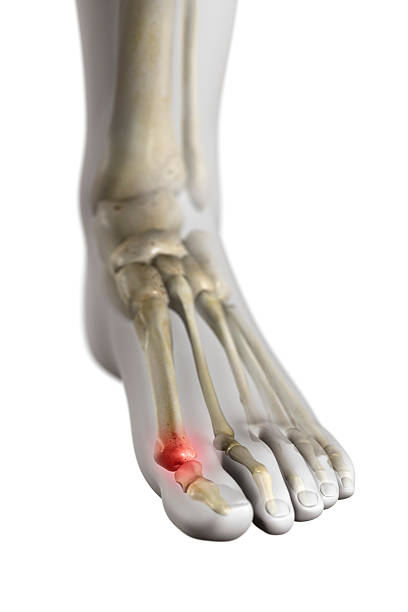

종자골염은 엄지발가락 아래쪽에 위치한 작은 뼈인 종자골(sesamoid bone)에 염증이나 통증이 발생하는 질환으로, 주로 반복적인 압력이나 충격으로 인해 발생합니다. 이 부위는 체중이 집중되는 부위 중 하나로, 보행이나 운동 시 지속적으로 자극을 받기 쉬우며, 특히 하이힐을 자주 신거나 달리기, 점프 등의 활동을 자주 하는 사람에게 잘 나타납니다. 종자골염은 초기에는 가벼운 통증으로 시작되지만, 시간이 지남에 따라 발바닥 앞쪽의 통증이 심해지고, 걸을 때 불편함을 초래하거나 발을 디딜 때 찌릿한 통증이 느껴지는 등 일상생활에 큰 영향을 미칠 수 있습니다. 본 글에서는 종자골염의 주요 원인 10가지를 중심으로, 나타나는 증상과 진단 방법, 그리고 효과적인 치료법과 재발 방지를 위한 관리법에 대해 구체적으로 살펴보겠습니다.

반복적인 압력과 충격은 종자골염의 가장 흔한 원인 중 하나입니다. 종자골은 발바닥 앞부분에 위치한 작은 뼈로, 걸을 때 체중을 분산하고 발가락을 움직이는 데 중요한 역할을 합니다. 하지만 지속적으로 뛰거나 걷는 활동, 딱딱한 바닥에서 오래 서 있는 직업, 무거운 짐을 자주 드는 일 등으로 인해 발바닥에 반복적인 압력이 가해지면 종자골에 미세 손상이 누적될 수 있습니다. 이러한 충격은 염증 반응을 유발하고, 통증이나 붓기, 보행 시 불편감을 초래할 수 있습니다. 특히 발 앞부분에 하중이 집중되는 보행 습관이 있거나, 체중이 많이 나가는 사람은 이러한 압력의 영향을 더욱 크게 받을 수 있습니다. 따라서 장시간 서 있거나 걷는 일이 많다면 발바닥에 가해지는 부담을 줄일 수 있는 신발 착용과 충분한 휴식, 스트레칭이 중요합니다. 이와 같은 생활 습관을 조절하지 않으면 증상이 점차 악화될 수 있으므로 조기 관리가 필요합니다.